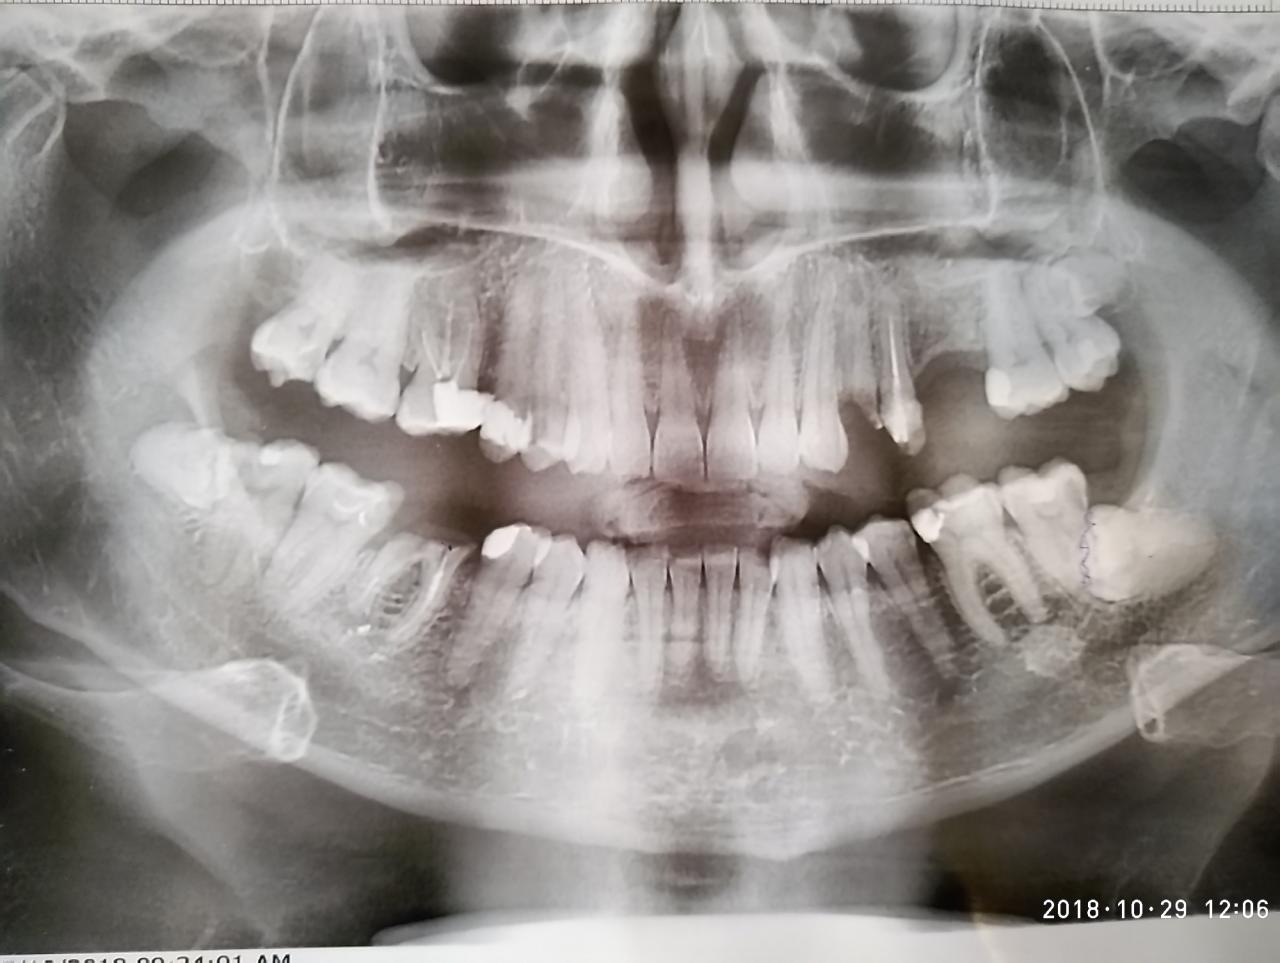

добрый день! посоветуйте с чего начинать? нужно ли депульпировать соседние зубы, чтобы делать мост сверху? нижнюю шестерку удалять?

зубы мудрости лучше удалять в челюстно-лицевой на слободке или можно у любого хирурга?

заранее спасибо всем за консультацию!

Нажмите на изображение для увеличения

Название: P81029-120600.jpg

Просмотров: 36

Размер:	95.9 Кб

ID:	12921077

Вложение 12921077

Начинать нужно с того, что определить, будет ли удаляться нижний шестой и верхний четвертый (конечное решение при осмотре у стоматолога в кресле), а затем, все что можно лечить - лечить/перелечивать/готовить для протезирования... В зависимости от выбора мостовидного протеза, опорные зубы либо депульпируют, либо нет. Такие зубы мудрости, как у Вас, не любой хирург может удалить.

четвертый уже удалили. шестой под вопросом. два врача сказали удалять. пару лет назад на шестом стояла коронка, но во время еды через время слетела. после этого зуб не укрывали коронкой. по восьмеркам одназначно удаление т.к. десна приоткрыта и один с кариесом. будем искать где удалять. стоимость примерно знаем, но для нас это дорого.

снимки мужа, первый раз делал обзорный снимок, поэтому для нас был сюрприз эти зубы мудрости